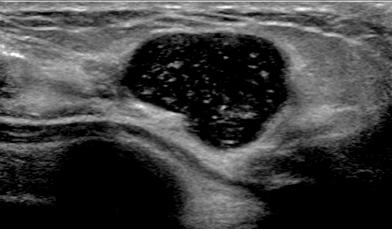

The target dataset was developed from 35 breast ultrasound scans that were segmented by an image-processing expert with extensive experience in breast lesion segmentation (the second author). The images, collected from the Web, are of different dimensions, ranging from to pixels (Figure 3, images resized for sake of illustration). These are the same images used to introduce EFIS originally [1].

Ultrasound images are generally difficult to segment, primarily due to the presence of speckle noise and low level of local contrast. It should be noted that the segmentation of ultrasound actually does require a complete processing chain, (including proper preprocessing and post-processing steps). However, the purpose of using these images was solely to demonstrate that the accuracy of the segmentation can be increased with the application of SC-EFIS.